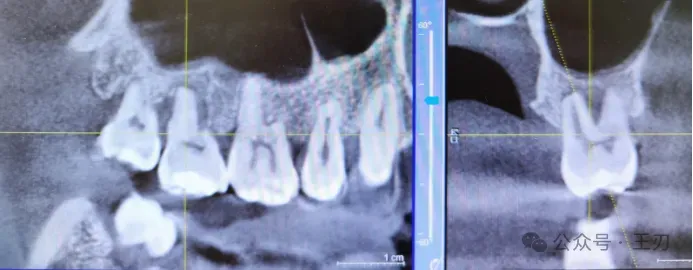

27的远中同样有探诊深袋,将视图拉到舌侧(上图),可以看到骨吸收,拉到颊侧(下图),看不到明显骨吸收。